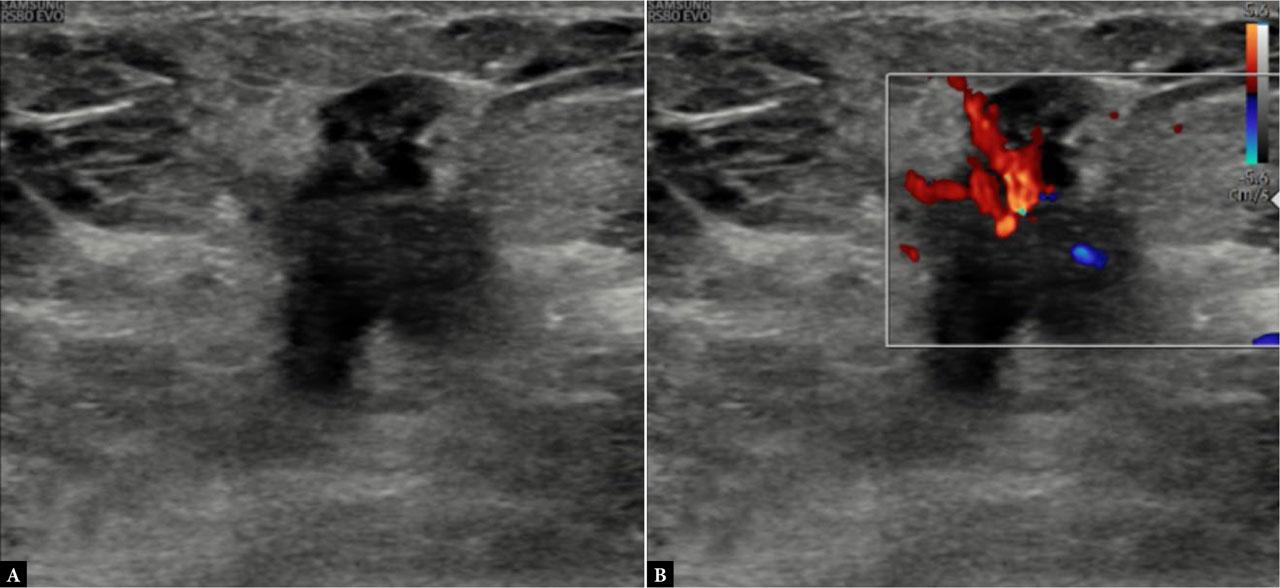

Fig. 2.